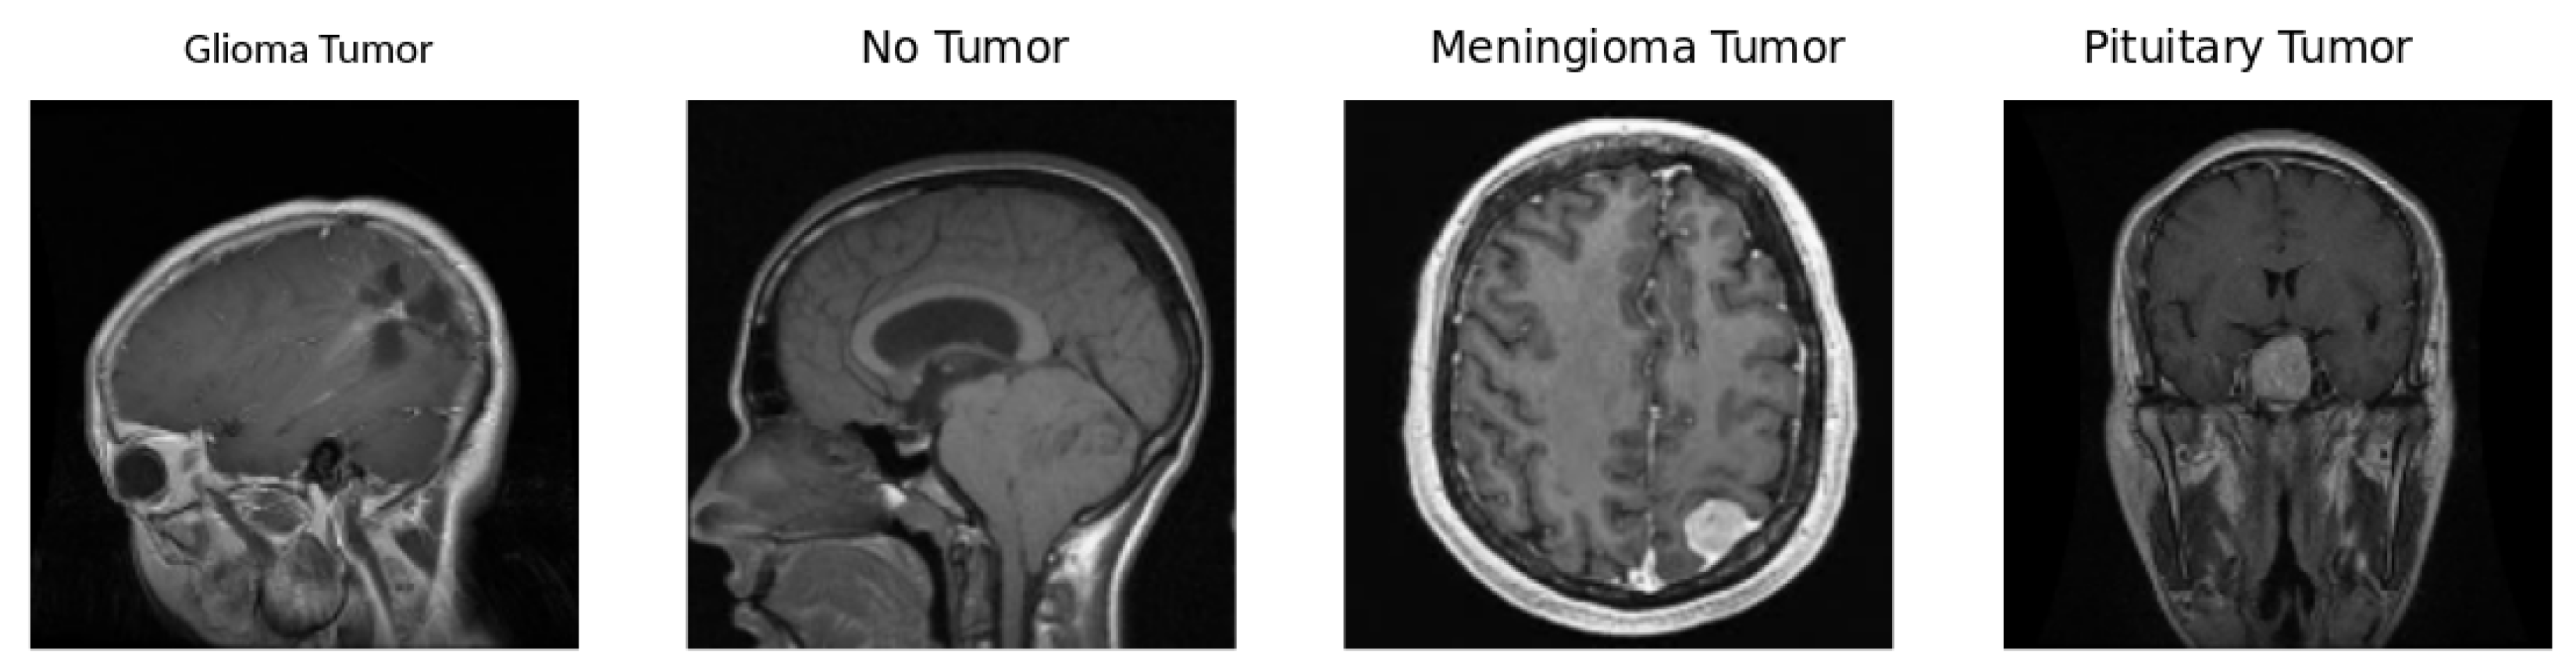

5.1. Dataset

- Brain tumor diagnosis: Diagnosing a brain tumor is a challenging process that requires the correct and rapid examination of MRI scan images. The study’s findings directly contribute to enhancing the accuracy and reliability of DL models for identifying brain tumors, focusing on this specific medical area. This is critical for early diagnosis and treatment planning for patients.